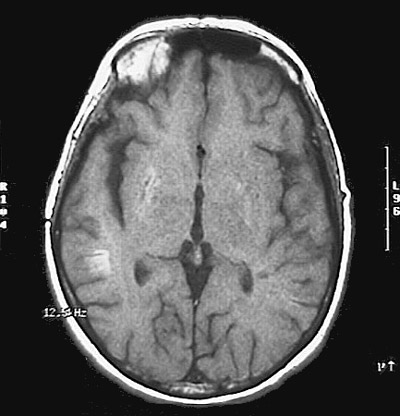

Click on the areas of infarction in the MRI scan below:

This magnetic resonance imaging scan demonstrates subacute infarctions in the right basal ganglia and also near the gray-white junction in the posterior parietal region.